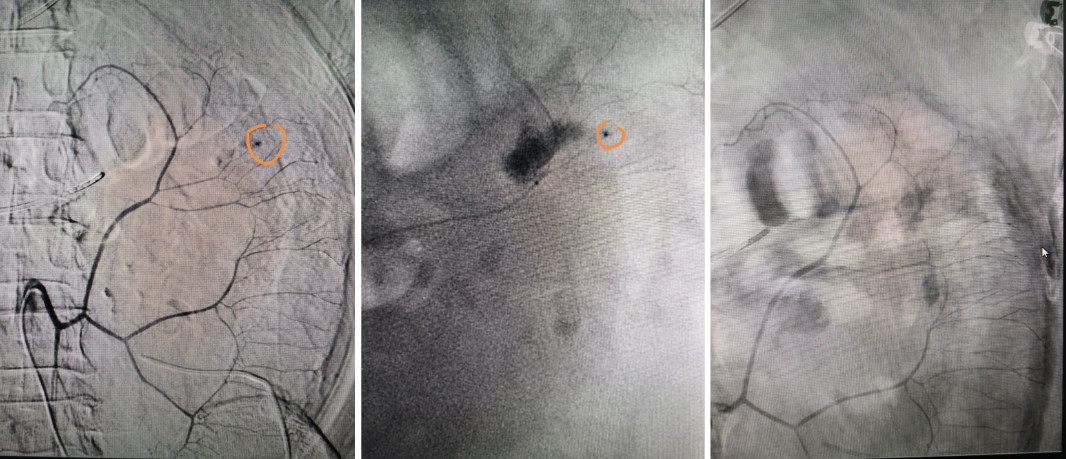

3月11日20:00左右,在告知患者家属病情及行急诊介入手术止血的必要性后,家属表示同意并签署手术同意书,随即患者被推入DSA手术室。放射介入团队张声旺、骆雷、郭睿、李心园迅速行经导管腹腔干动脉、肠系膜上动脉、肠系膜下动脉造影,术中造影发现结肠脾曲区域肠系膜下动脉三级小分支的末梢出血。明确出血责任血管后,考虑到结肠脾曲侧支循环相对较少,如果介入栓塞系膜动脉范围稍大就会造成肠缺血坏死、栓塞范围稍小就不能有效止血,栓塞靶血管必须非常精准才有可能有效止血并避免肠缺血坏死。放射介入团队在仔细、冷静分析患者血管具体情况后,通过微导管超选择插管并注入栓塞剂,栓塞后造影显示完全止血后患者返回EICU。介入术后患者一般情况明显好转,血红蛋白逐渐升高,3月16日患者复查腹部CT报告结肠脾曲系膜区域未见活动性出血,且结肠脾曲未见缺血征象。